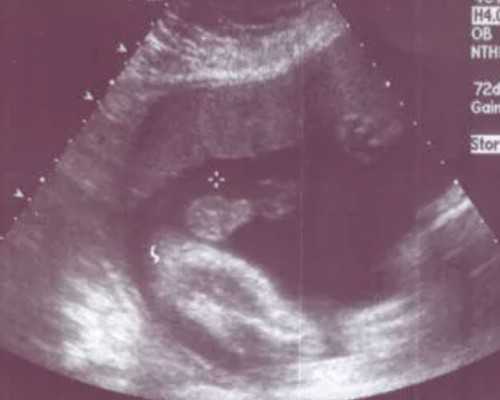

3.手术及实验室*作:1-3万元左右。实验室*作包括体外受精、胚胎培养、胚胎移植。医生根据女性的身体情况决定是否适合移植双胎,如果适合移植双胎并且移植的两个胚胎都存活,那么就是双胞胎。